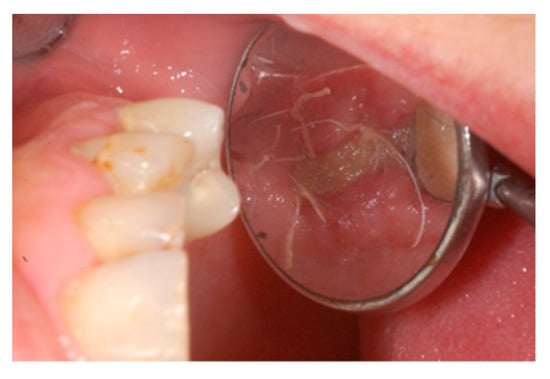

We used only surgical discarded material for the present study and the subject gave her informed consent before her participation. Seven days before the tooth extraction, the patient started prophylactic antibiotic therapy with amoxicillin/clavulanic acid (Augmentin, GlaxoSmithKline, Verona, Italy) and continued it for seven days after surgery 1 g/every 12 h, in addition to mouthwashes (chlorhexidine 0.2%) starting a week before surgery and continuing until healing occurred. Figure 2 shows the clinical situation after the crown removal. Once the extraction of tooth 26 (Figure 3) was carried out, the preservation of the alveolus was performed using a commercial enzymatically-deantigenated equine bone (Osteoxenon bone granules, Bioteck S.p.A, Vicenza, Italy) (Figure 4) and a commercial double layer of equine pericardium membrane (Heart pericardium membrane, Bioteck S.p.A., Vicenza, Italy) was used to cover and protect the site (Figure 5).

Figure 2.

Clinical situation after crown removal.